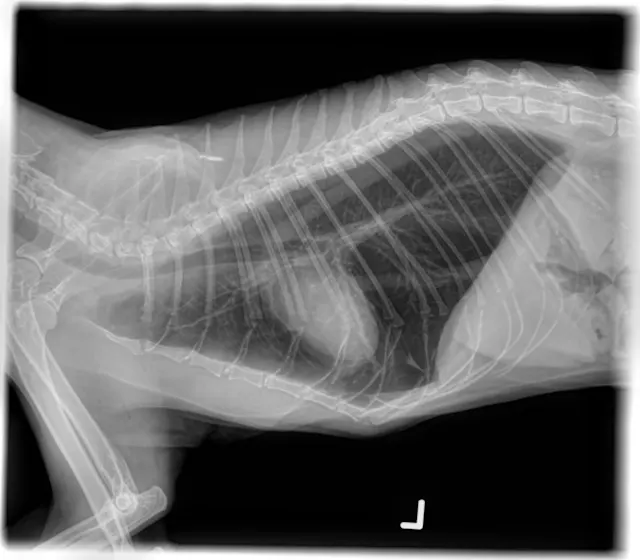

• Radiographs: Persistent hyperinflation but with improvement from initial study

Radiographic Interpretation

Pneumothorax was diagnosed here based on the elevation of the heart from the sternum, which can be one of the signs of pneumothorax. However, it is extremely important to look at the entire radiograph.  In these, (see images) the lung fields can be followed to the edge of the chest cavity on both the lateral and ventrodorsal views: there is no air surrounding the lung lobes. Although the heart looks raised, the area ventral to the heart on the lateral images shows a soft tissue opacity (possibly fat), not air. The lungs are hyperinflated, which is consistent with primary lung disease and not a typical sign of pneumothorax.

The hyperinflated lungs and bronchial pattern in the radiographs are consistent with primary pulmonary disease. Possible causes could include feline asthma, parasitic disease such as heartworm or other infestation, or toxoplasmosis.  An endotracheal wash with cytology and culture, fecal testing (Baermann), and toxoplasma testing would all be considerations.  A heartworm test that was performed was negative.